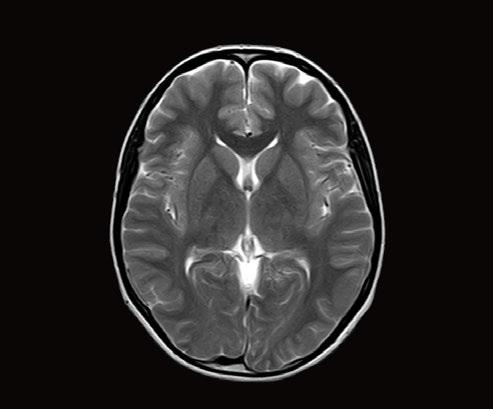

In particular DLR has an important clinical impact in anatomical regions that require a very high resolution, for example parts of the hippocampus and the claustrum.

“The DLR brings a spatial resolution that I have never seen before in neurologic imaging. I recently pointed out a brain area, for example the claustrum, that is almost invisible on standard MRI images even with very high resolution or high field devices. However, thanks

to the DLR we could highlight this kind of brain anatomy. So, indeed, there is a considerable advantage to using this technique.” Prof. Dousset said.

Prof. Tourdias worked at 7T to visualise extremely fine structures of the hippocampus while at Stanford. With DLR, he can now do this task with a 3T. “When we compared the images we realized that by pushing the 3T machine and processing with DLR that we were able to achieve a similar result to what we could achieve with 7T. I think this is the main surprise of the technology.” he said.

Atlas SPEEDER Head/Neck, T2, AiCE, Res: 0.2 x 0.2 x 2 mm, Scan time: 6:35 min.

Brain – Hippocampus